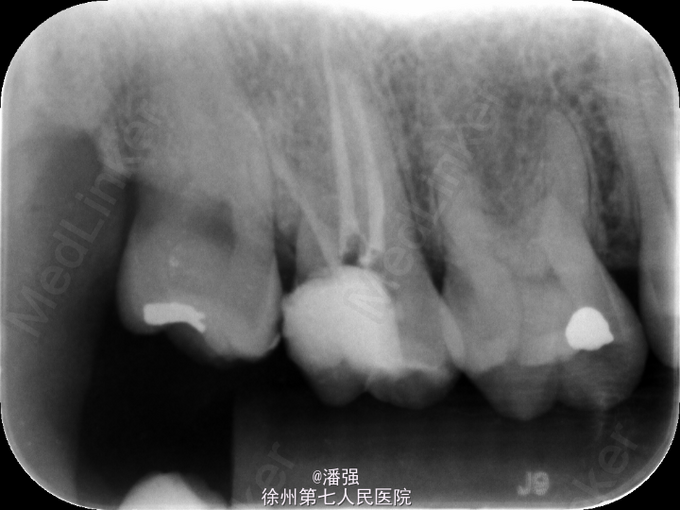

诊断 处理

17慢性牙髓炎,处理,去腐未尽穿髓,局麻下开髓揭顶,远中腐质去完,平齐牙龈,通根,封药,复诊,根管预备,完成根管充填

随访 讨论

远中龋损不易被发现,每次去完腐质,可到龈下,可用玻璃离子形成假壁,减少微渗漏